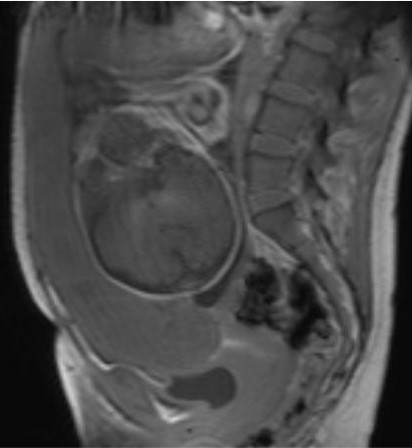

Завершающий, или «тазовый» этап, длительностью не более 5–10 мин, при котором прицельно оценивается нижние сегменты матки, внутренний зев, шейка матки, мочевой пузырь, смежные ткани и органы таза беременной с целью выявления критериев прорастания плаценты, которые могут соответствовать 3 (a, b, c) степени согласно классификации FIGO (2018) для клинической диагностики группы плацентарных нарушений адгезивно-инвазивного спектра (рисунок 2).

| Рисунок 2 – Беременность 36 нед. МРТ плаценты. Основной, «плацентарный» этап исследования. Варианты позиционирования срезов для получения ортогональных изображений плаценты в косо-сагиттальной (б), косо-корональной (в) и косо-аксиальной (г) плоскостях относительно анатомии беременной по МР-изображениям первичного этапа (а) | ||